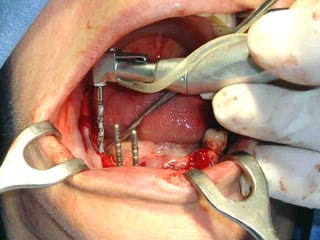

Segundo tiempo quirúrgico para aplicar la estructura.

Estructura en íntimo contacto con la superficie ósea, quedando los postes

fuera de la fibromucosa gingival..

Sutura de colgajos que cubren la estructura, dejando los postes bien visibles.